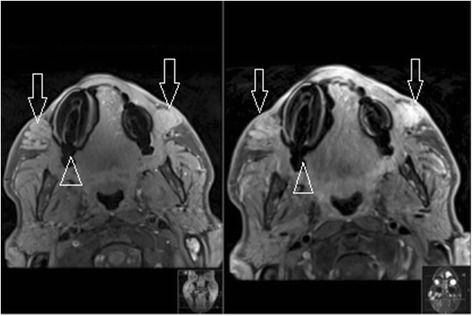

Although substances such as silicone and hyaluronic acid have distinct MRI signatures because of their very high or low water content (Fig. 1), intermediate substances tend to produce a more ambiguous image. T1 and T2 Dixon fat suppression with high resolution small FOV MRI make it possible to better visualize and identify these substances (i.e., collagen, Fig. 2). Our original algorithm as summarized in Table 1 which differentiates common fillers in terms of their MRI characteristics, provides a simple guide to assist radiologists in their analysis.

Fig. 1.

Polyacrylamide gel axial dermal filler appearance in both infraorbital triangles (open arrows) on axial MRI (T1FS, T1 FS with gadolinium). Note the susceptibility artifacts from dental implants (open arrowhead) while the filler’s signal intensity remains high before and after injection of gadolinium